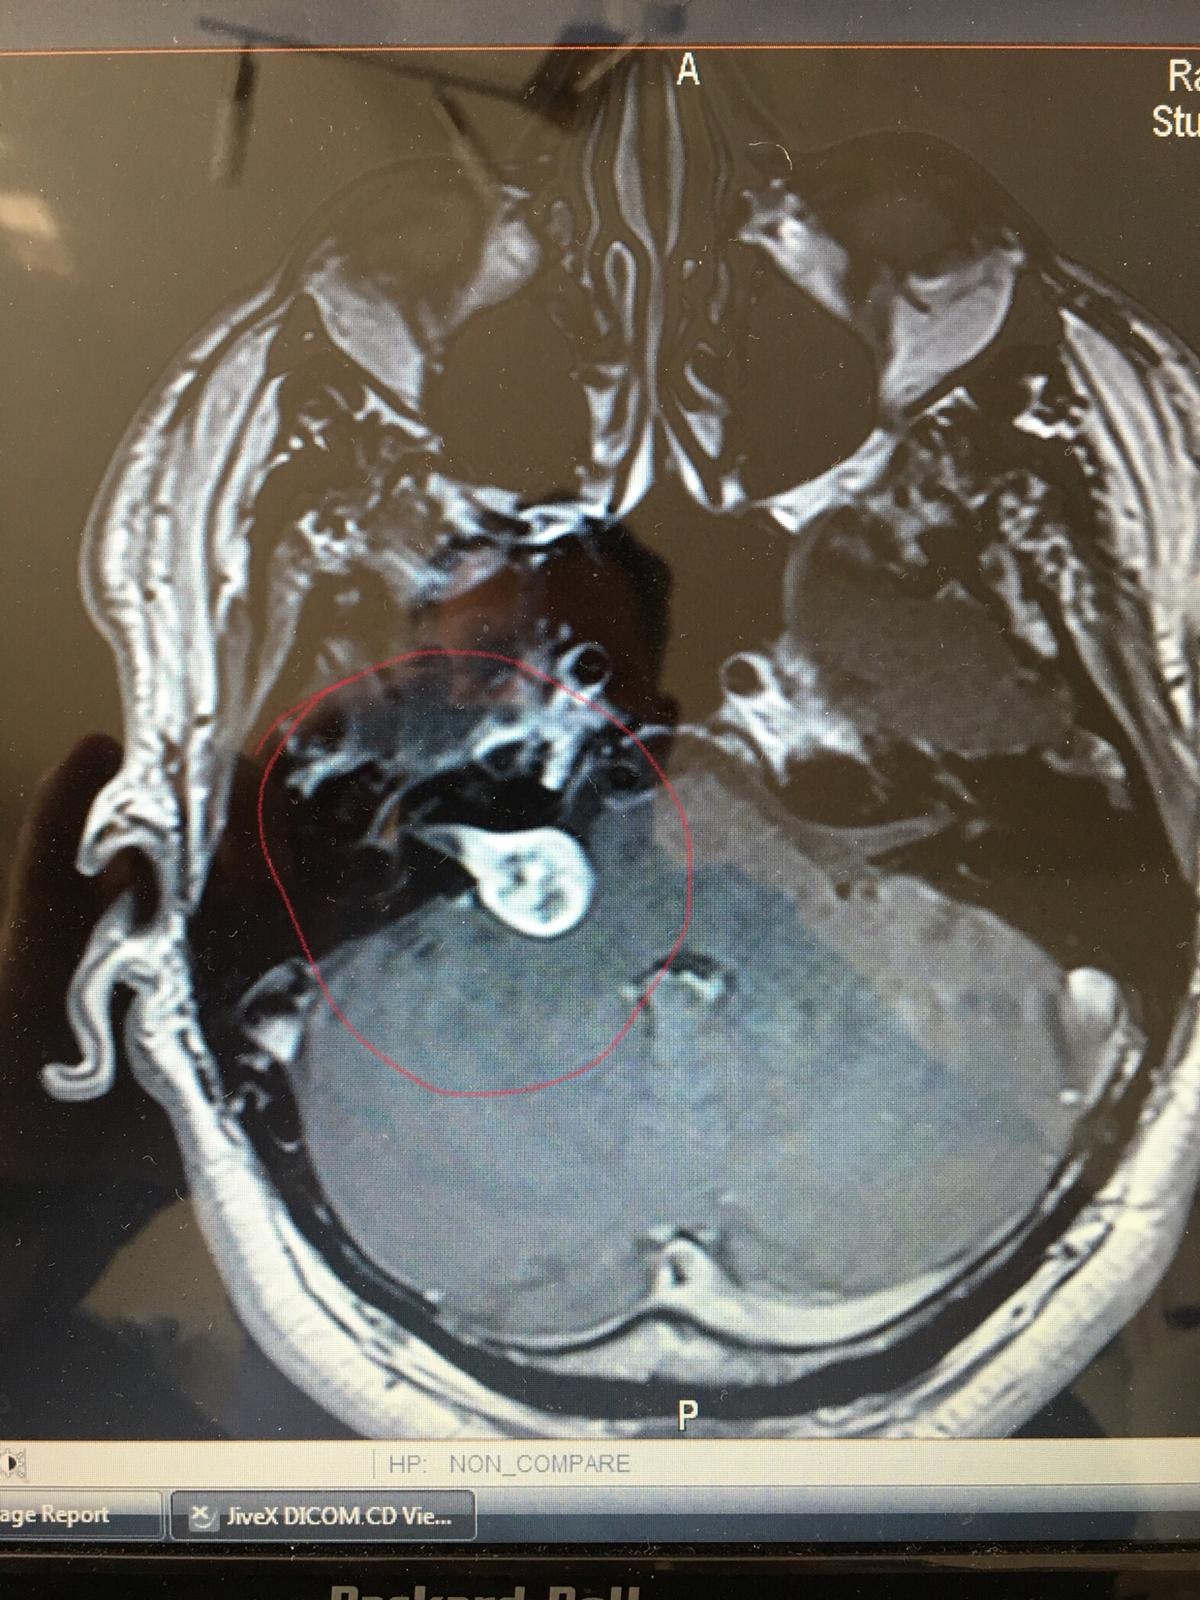

Der letzte große Schlag gegen mein Comeback was leider ein Hirntumor. Aber aktuell, ca. ein Jahr nach meiner OP ist alles gut.

49144903_10213041894304305_2463872138981933056_o.jpg

48944717_10213041893984297_4858891476853063680_o.jpg

Warum ich darauf eingehe, dieser Tumor war auch der Grund, warum ich aufgehört hatte. Mir ging es damals sehr schlecht und ich wusste nicht warum. Hatte kaum die Kraft einen Turn auf dem Motorrad zu sitzen und es wurde gefährlich. Also habe ich es gelassen als noch andere Dinge dazu kamen. Erst Jahre später, wurden von den Ärzten der Tumor und der Grund für meinen körperlichen Abbau bekannt. Heute geht es mir gut!